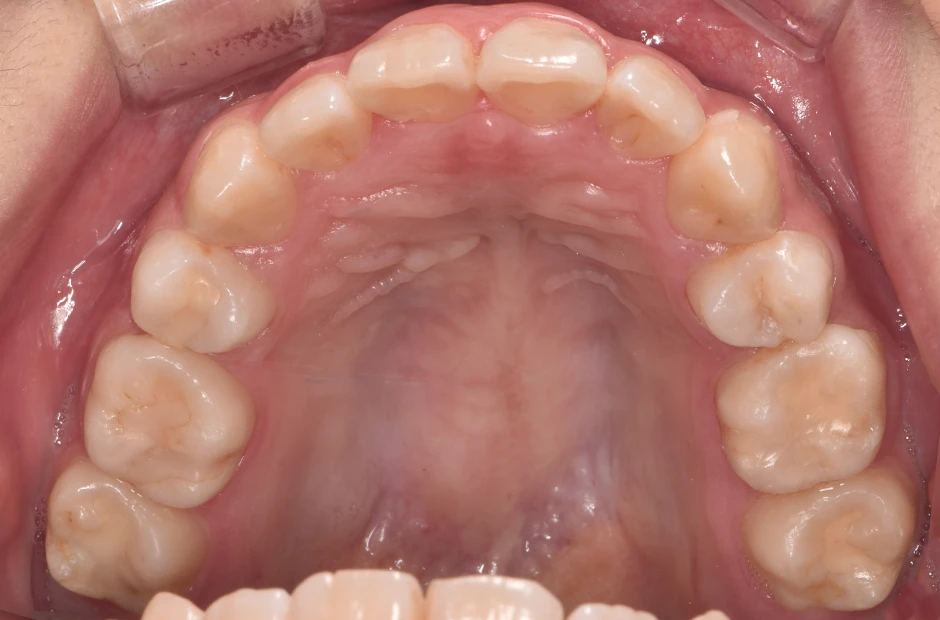

治療症例

ブラケット矯正

前歯部反対咬合

| 診断名・主訴 | 前歯部反対咬合 |

|---|---|

| 年齢・性別 | 14歳・男性 |

| 治療期間・回数 | 1年2か月 |

| 治療に用いた主な装置 | ブラケット矯正 |

| 抜歯部位 | なし |

| 治療費 | 60万円(税抜) |

| リスク・副作用 | 装置による違和感・疼痛・歯肉退縮・歯根吸収・虫歯のリスクなど |

治療後